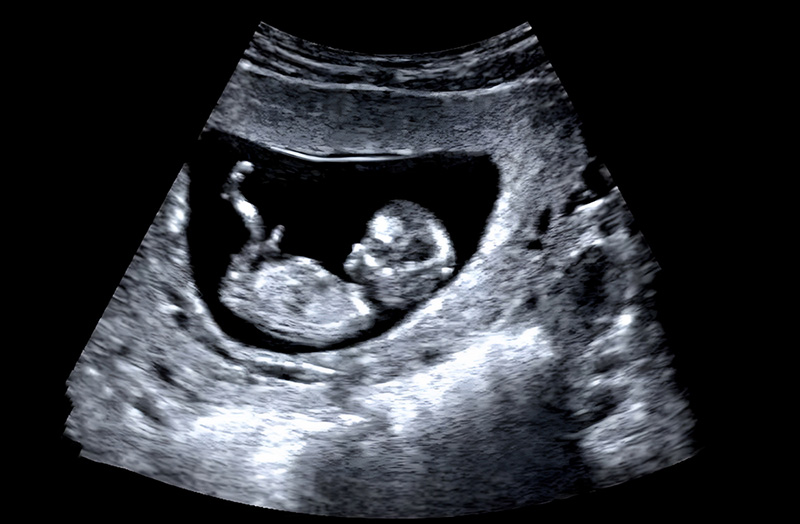

ลูกดิ้นแค่ไหนถึงเรียกว่าปกติ ? คู่มือคุณแม่มือใหม่ สังเกตอาการลูกรัก พร้อมวิธีกระตุ้นให้ลูกดิ้น